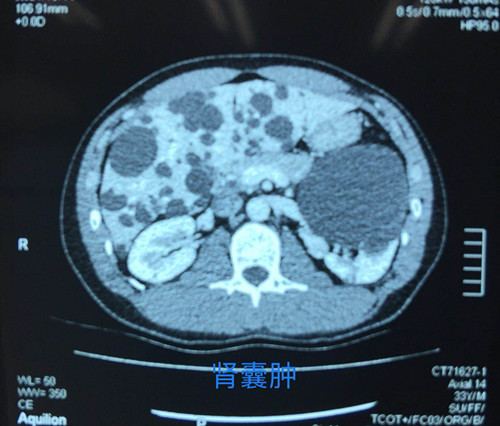

泌尿外科手术效果图